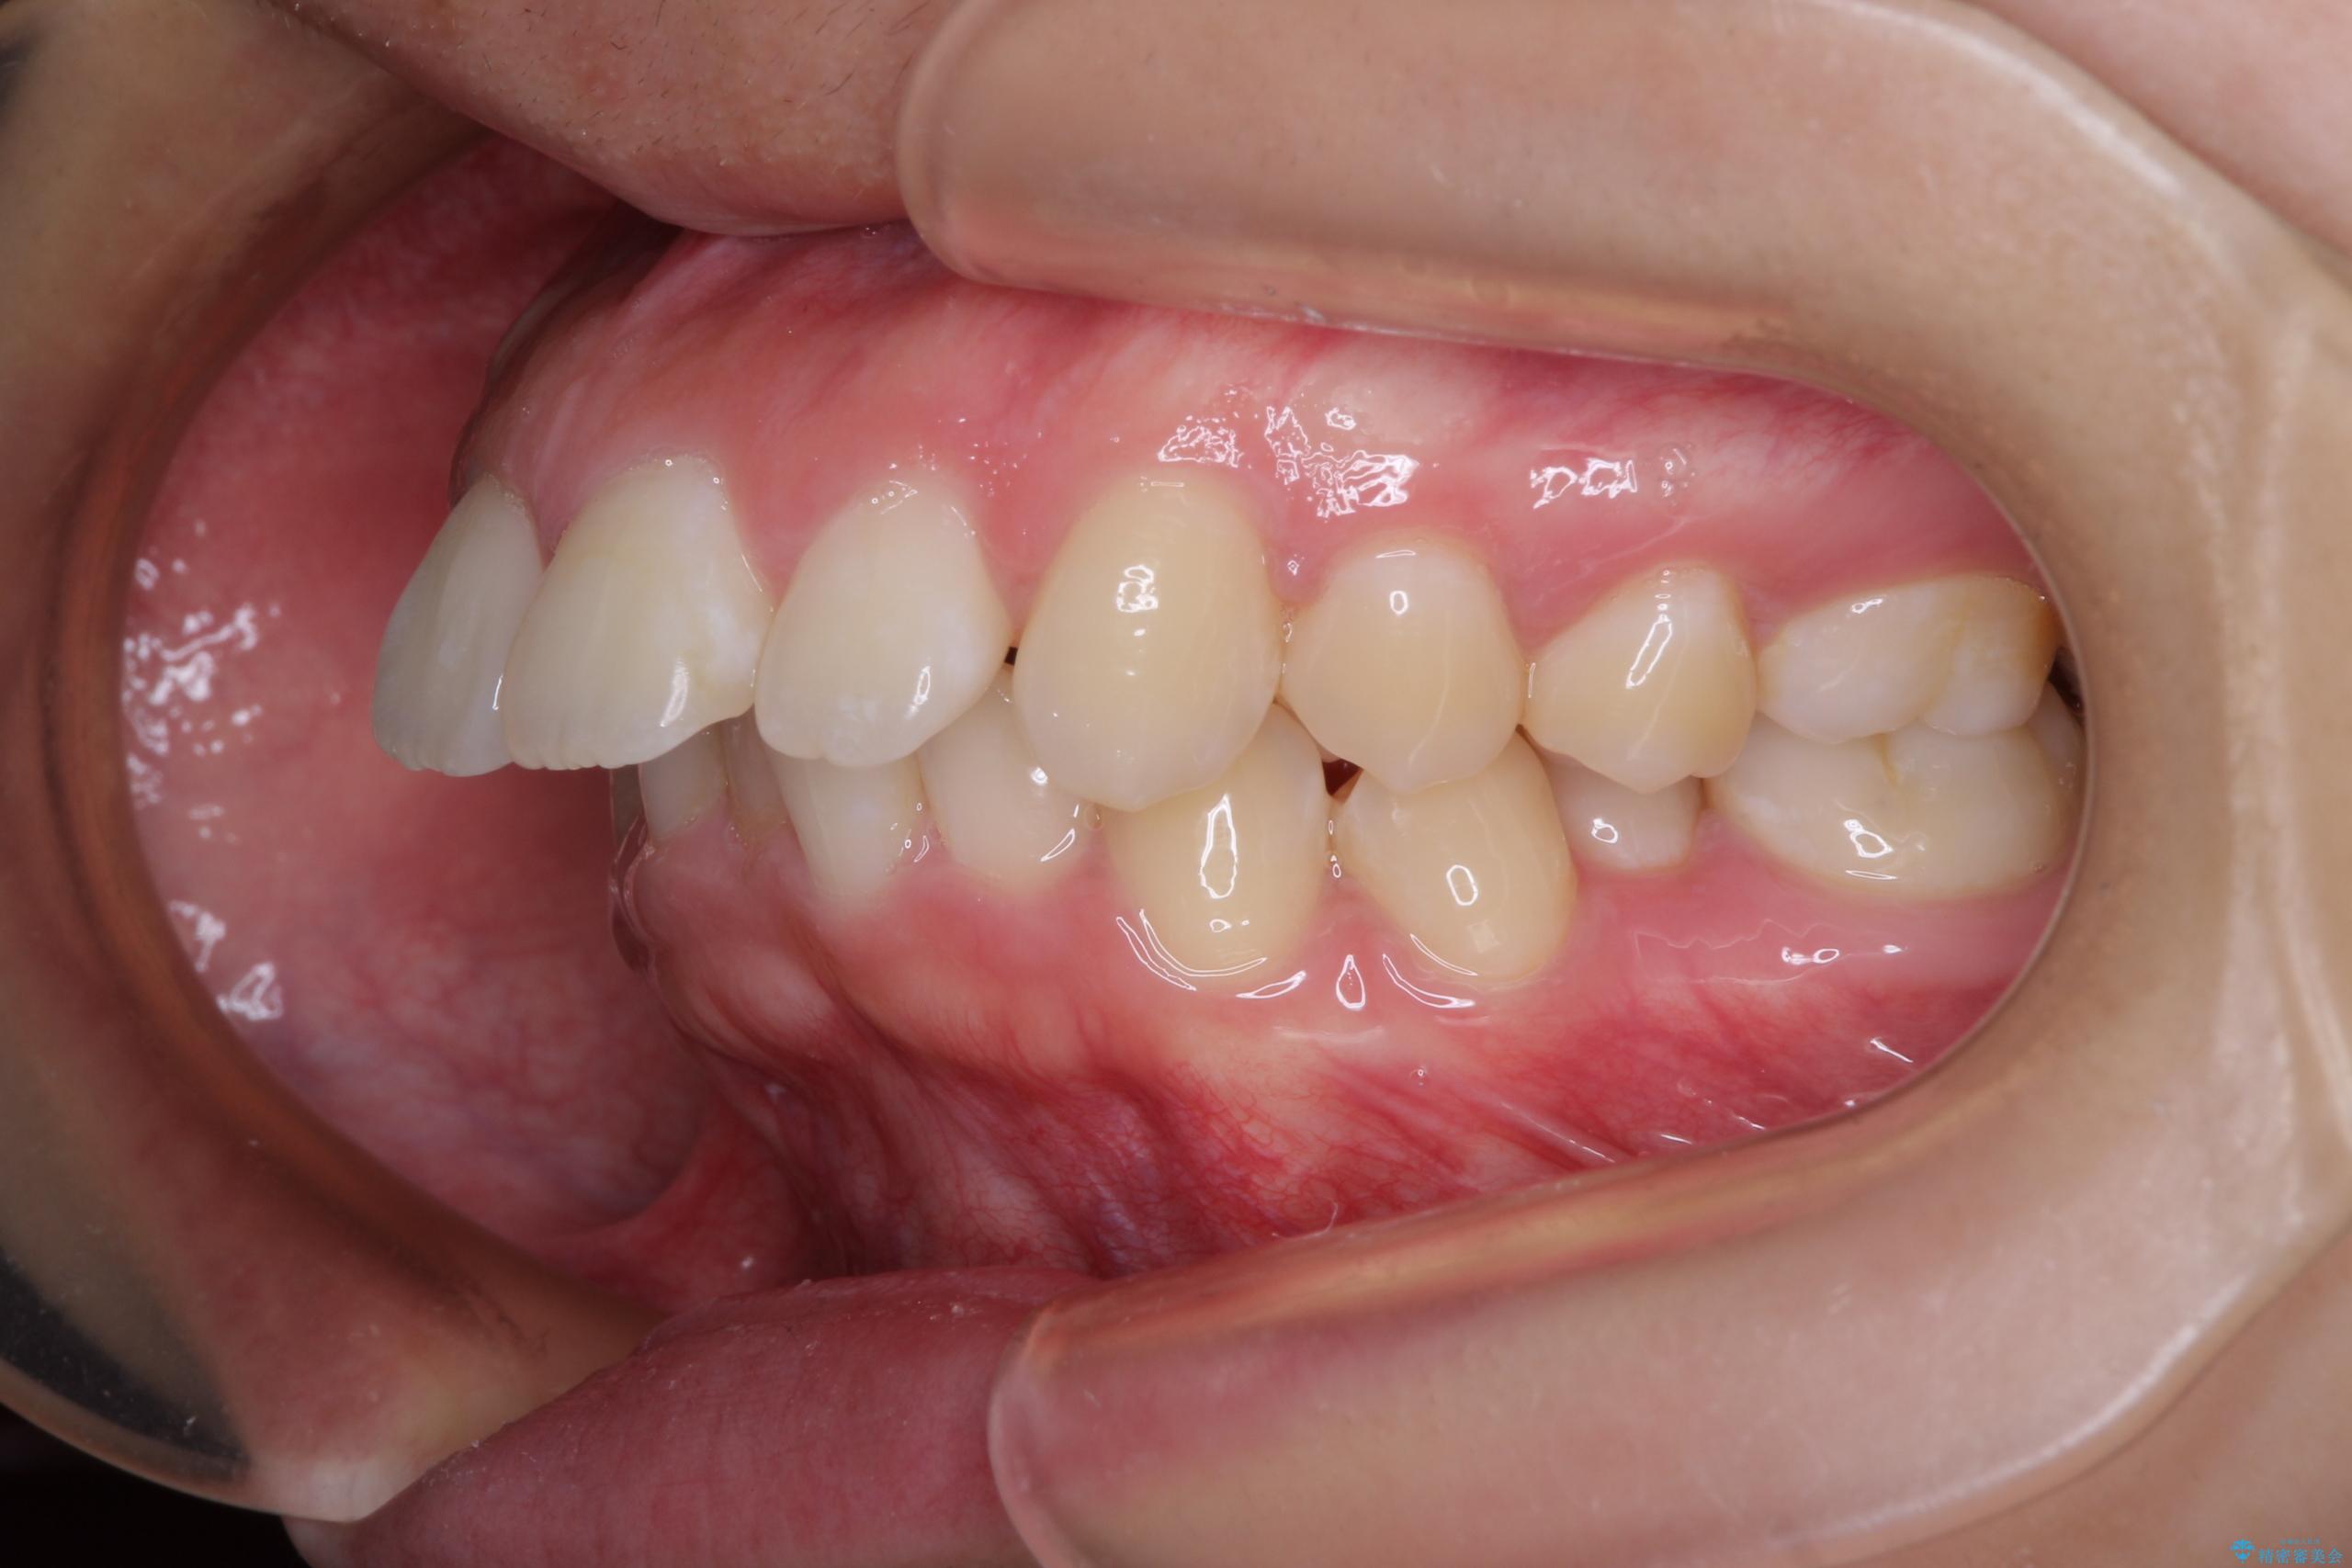

- 上顎前歯が飛び出していて唇がうまく閉じられないとのことで来院された患者様です。

くちばしのように前歯が突出していたため、口元を積極的に引っ込めるために、上下左右の小臼歯4本を抜歯することとしました。

また、上顎歯列が下顎に対して前方位に位置していたため、補助装置を用いて上顎歯列を後方に移動させ、より積極的に口元を下げるようにしました。